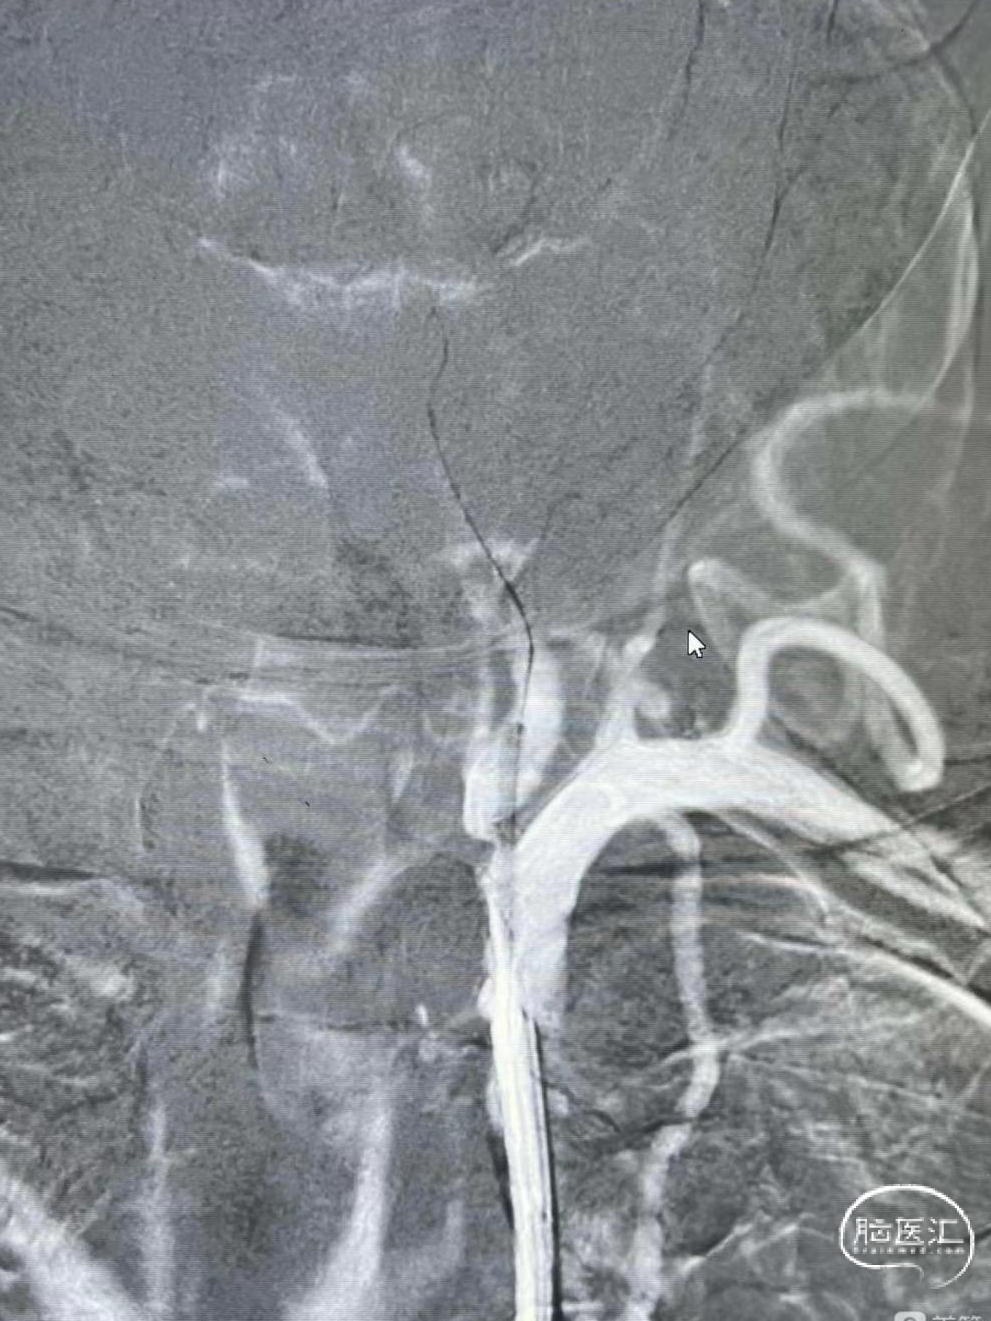

保留微导丝、Guiding回撤到锁骨下,观察椎动脉开口:椎动脉开口无法维持。拟行椎动脉开口支架成形术,选用4mm*15mm Bridge椎动脉雷帕霉素靶向洗脱支架。

操作要点:

释放后注意严格控制血压,球囊不急于撤出,可逐步泄压。

6

术后造影:

血管再通,前向血流3级。左侧为胚胎型大脑后。

术后用药:替罗非班24小时复查CT后桥接双抗。

术后CTA:Bridge药物支架形态良好,前向血流良好。